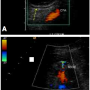

A 36-year-old previously healthy Caucasian woman with longstanding history of tachypalpitations underwent electrophysiological study and AV node re-entry tachycardia (AVNRT) ablation using the left femoral vein approach. Two large-gauge 8 and 10 Fr sheaths were used during the procedure. Her immediate postprocedure course was uneventful. She presented one month later complaining of numbness and tingling in her left foot, with local edema and mild groin discomfort. Pedal pulses were intact and no obvious abnormality was noted on examination of the foot. Lower extremity duplex scan revealed a left common femoral artery pseudoaneurysm (2.2 x 2.3 cm) that had almost completely thrombosed, with a small amount of residual to-and-fro flow (Figures 1A and 1B). It was decided to conservatively manage the pseudoaneurysm, expected to spontaneously thrombose. A few days later the patient presented to the office with complaints of worsening pain in her left leg and foot, which was elicited by even light touch, as well as continued localized swelling and cold sensation. On examination the patient’s foot showed significant coolness, mottling of the skin most notable over the 3rd and 4th toes, mild edema, and normally palpable dorsalis pedis and posterior tibial pulses. We suspected distal embolization from the known femoral pseudoaneurysm. However, repeat duplex scan showed that the pseudoaneurysm had completely thrombosed with normal flow in the common and superficial femoral arteries (SFA) as well as the infragenicular arteries. The patient was started on aspirin and clopidogrel.